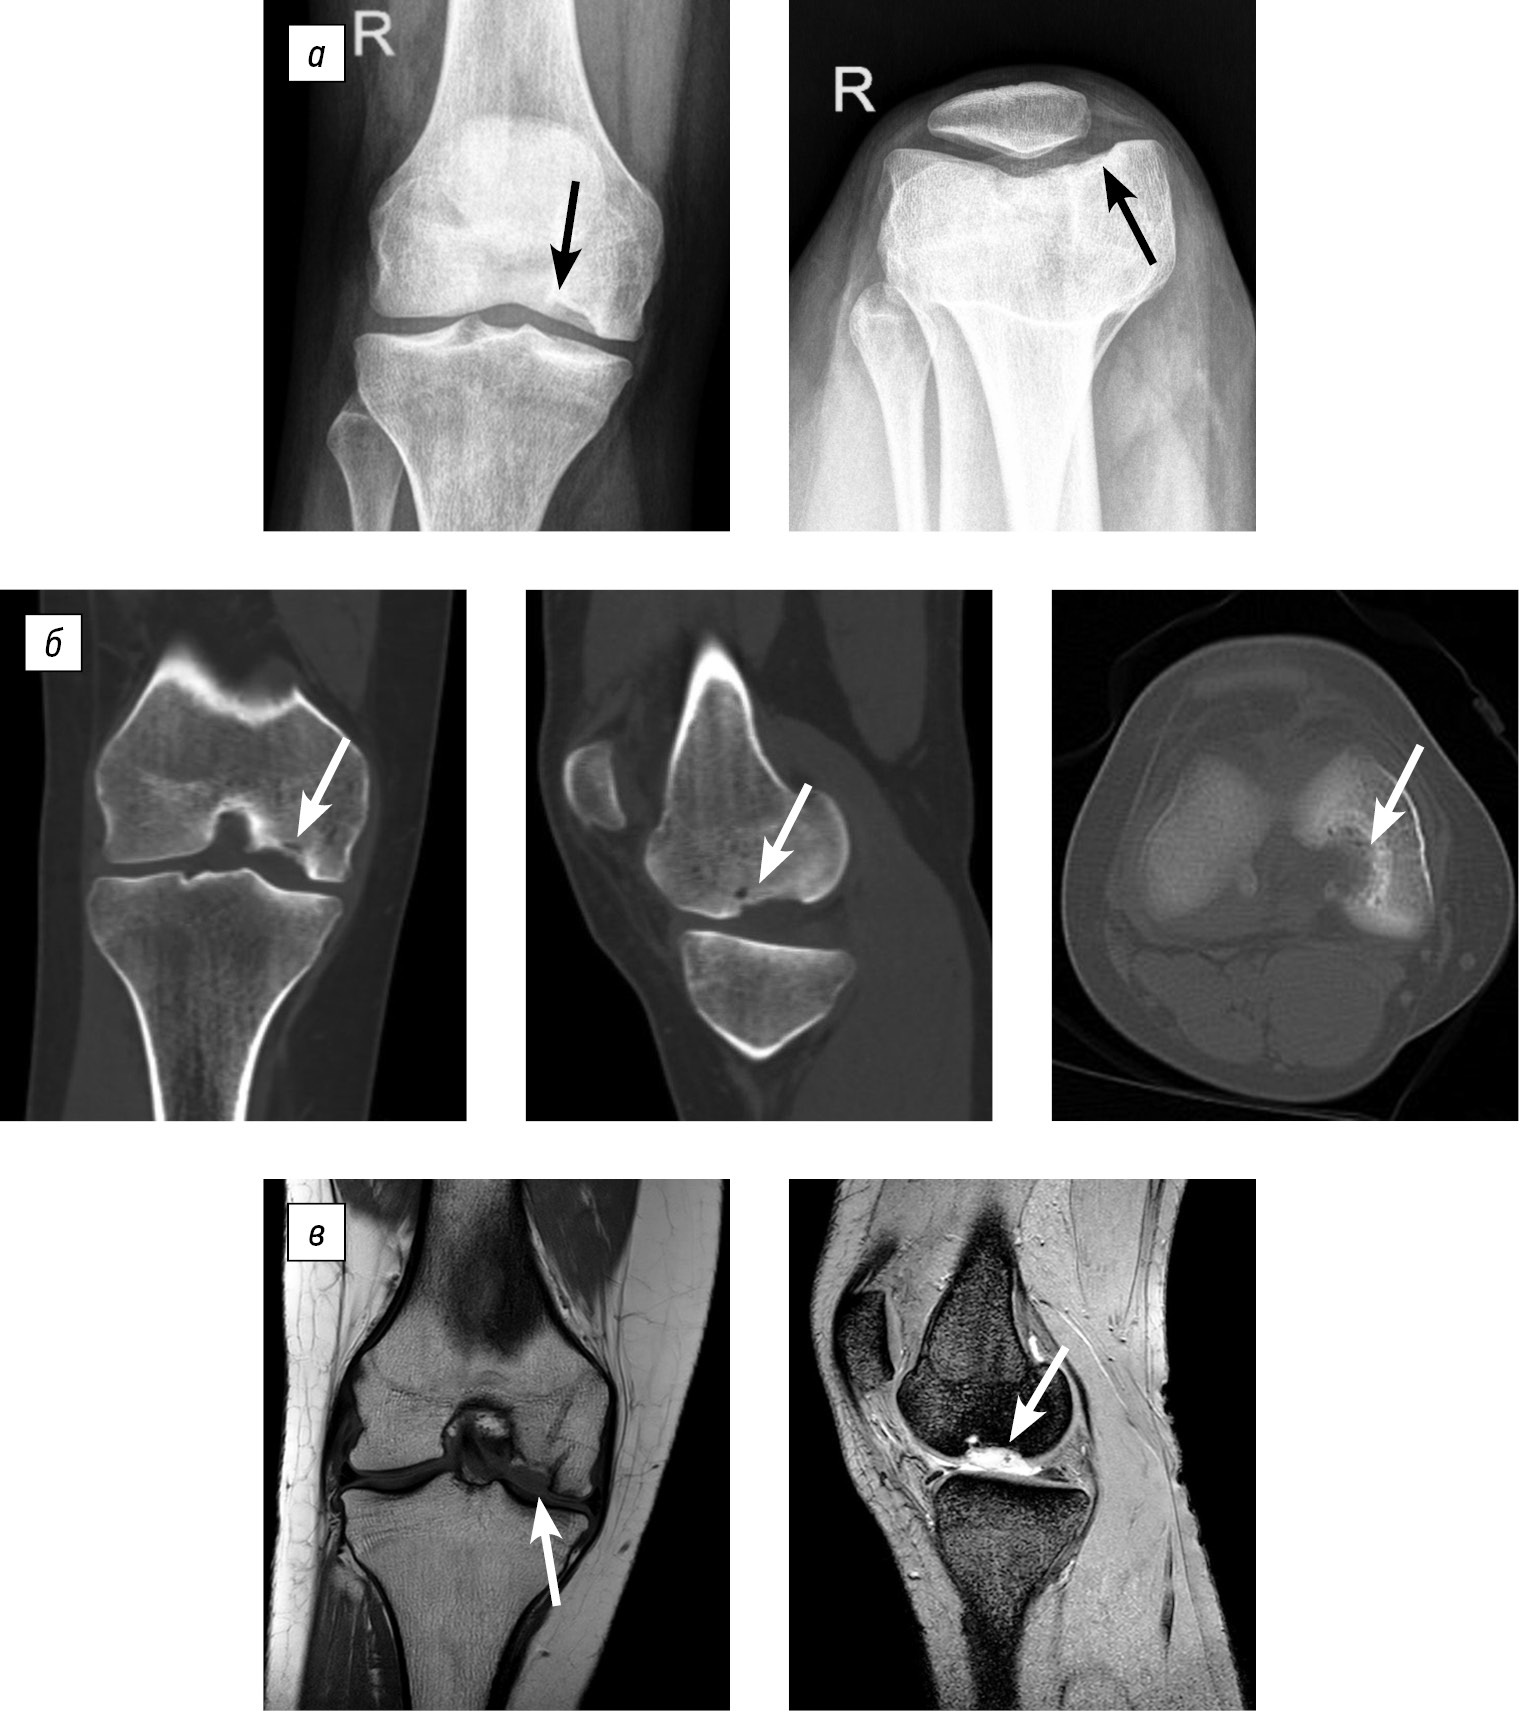

Clinical evaluation was performed 2.5 years after the surgery. The patient reported no active complaints. She experienced occasional pain in the right knee joint after prolonged walking (for more than 2–3 km). The range of motion in the knee was full and painless. Functional scores: Lysholm, 92 points; KSS, 95 points (Fig. 4).

Fig. 4. Follow-up clinical and imaging evaluation of patient B at 2.5 years after reconstruction: a, range of motion in the right knee joint; b, magnetic resonance images in the frontal and sagittal planes.